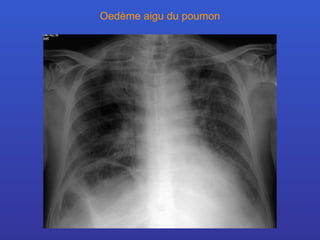

Oedème aigu du poumon